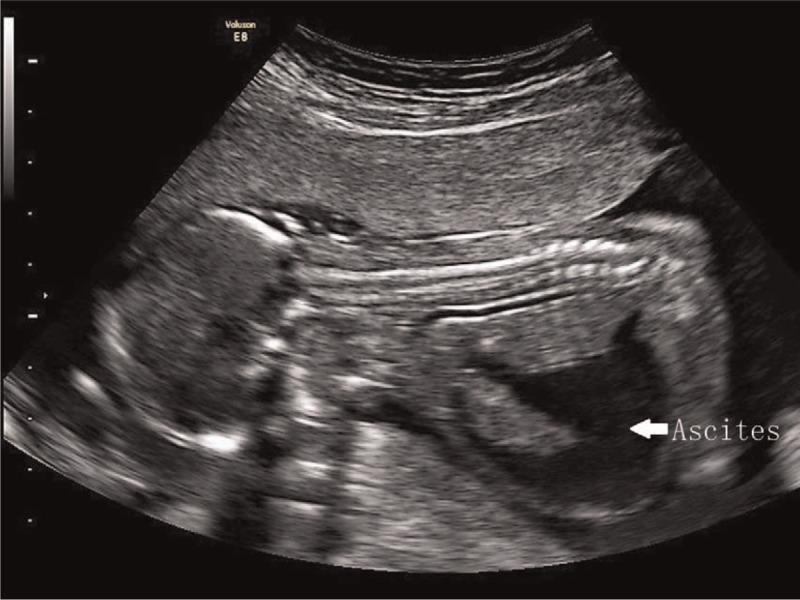

The prenatal phenotype of case 1 included sonographic markers such as enlarged nuchal translucency (NT), absent nasal bone, short femur and humerus length, and several structural malformations involving Dandy-Walker malformation and congenital heart defects. The prenatal phenotype of Case 2 are sonographic markers, including enlarged NT, thickened nuchal fold, ascites, and polyhydramnios without apparent structural malformations.

Conventional G-band karyotype appears normal in case 1, while it shows normal chromosomes with a small supernumerary marker chromosome (sSMC) in case 2. Genetic etiology was left unknown until single-nucleotide polymorphism-based array (SNP-array) was performed, and segmental paternal UPD 22 was identified in case 1 and segmental paternal UPD 14 was found in case 2.